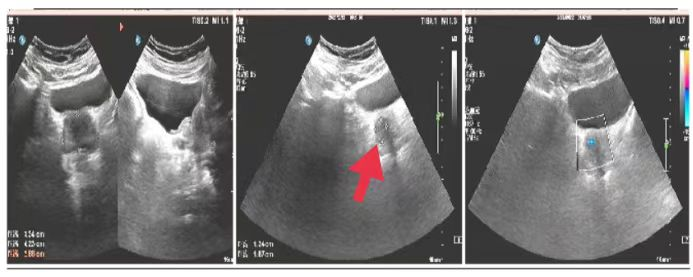

03、**男士,73岁

于2023年10月3日在邯郸仁泰北区体检。实验室检查提示:前列腺特异抗原(PSA)23.17 ng/ml。前列腺彩超检查提示:前列腺稍大,实质回声欠均匀,内可见稍低回声,大小约1.3*1.6cm,边界欠清,内回声欠均匀,CDFI:可见点状血流信号,建议客户到三甲医院进一步检查。2023年10月17日电话回访,客户家属告知,已到三甲医院进一步检查等待结果,2023年10月29日跟踪回访,客户家属告知,客户已在省某三甲医院手术治疗。